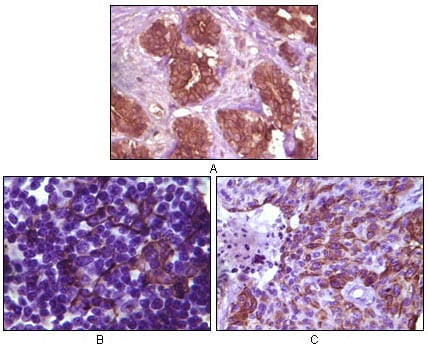

分类: 科研抗体货号: 20084别名: SR; BCSG1应用: IHC反应种属: Human

分类: 科研抗体货号: 20089别名: DKFZp686D0638; GSK3A应用: IHC反应种属: Human

分类: 科研抗体货号: 20101别名: ELK1应用: IHC反应种属: Human